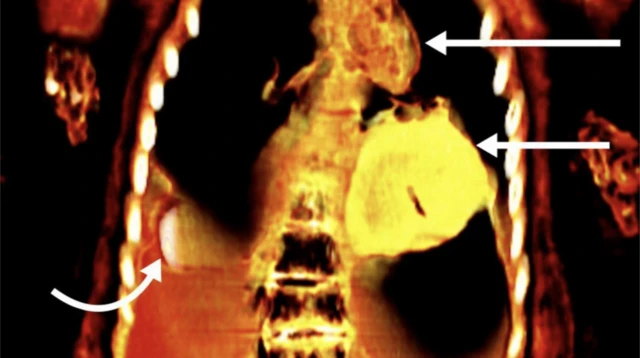

යෞවනයාගේ සිරුර වෙලා තිබූ වෙළුම් පටිවලට යටින්, චර්මච්ඡේදනය නොකළ ඔහුගේ ලිංගය අසල ඇඟිලි දෙකක් පමණ දිගු වස්තුවක් තිබූ බව එම ඡායාරූපවලින් පෙනී ගියේ ය. ඔහුගේ මුඛය තුළ රනින් කළ දිවක් ද, උරස් කුහරය තුළ රනින් කළ, හදවත් හැඩැති ස්කැරැබ් කෘමියෙකු (පුරාණ ඊජිප්තුවේ ආගමික සංකේතයක් වූ ගොම කුරුමිණියෙක්) ද විය.

වෙනස් වර්ග 21කට අයත් සුර වැනි බලගතු පළඳනාවන් 49ක් මියගිය පුද්ගලයාගේ සිරුරට පළඳවා තිබූ වග ස්කෑන් ඡායාරූපවලින් හෙළිවූ අතර, එයින් බොහොමයක් රනින් සාදා තිබුණි. මෙනිසා මෙම මමිය 'ගෝල්ඩන් බෝයි' (ස්වර්ණමය කොලුවා) ලෙස හැඳින්වෙනබව, ෆ්රොන්ටියර්ස් ඉන් මෙඩ්සින් නම් ජර්නලයේ පළවූ ලිපියක් හරහා ආචාර්ය සලීම් නිවේදනය කළේ ය.